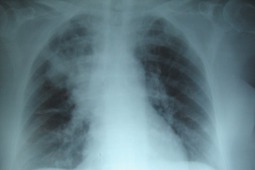

Zastosowanie lumakaftoru i iwakaftoru u pacjentów z mukowiscydozą i zmianami płucnymi

Leczenie skojarzone iwakaftorem i lumakaftorem prowadzi do wzrostu wartości wskaźnika FEV1 u pacjentów będących homozygotami względem delF508/delF508. Konieczna jest jednak ocena bezpieczeństwa, tolerancji i skuteczności lumakaftoru i iwakaftoru, szczególnie u młodych pacjentów z mukowiscydozą z towarzyszącą ciężką chorobą płuc.